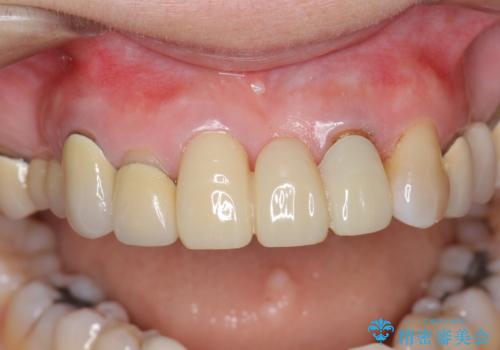

前歯ブリッジのやりかえ

- 前歯の審美障害、見た目の改善を希望され来院されました。

- 47万円(仮歯×3・ファイバーコア×2・ジルコニアクラウン×3 歯の挺出)費用は治療当時の料金となります